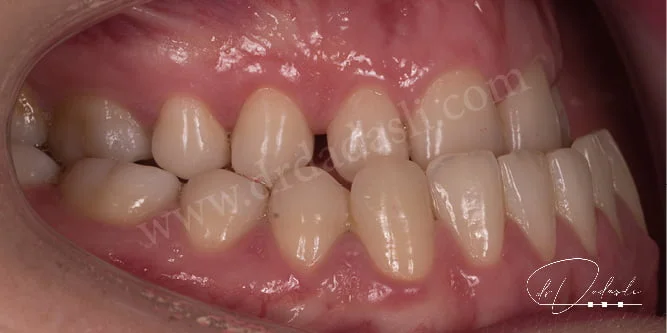

- Çapraz kapanış (Şekil 4) – normal şartlarda üst dişlerin alt dişleri kutu kapağı gibi örtmesi gerekir. Yani üst çene alt çeneden daha geniştir. İşte üst çene alt çeneye göre dar olduğu durumlara çapraz kapanış ismi verilmektedir. Çapraz kapanışı olabildiğince erken yaşta tedavi etmek gerekir.